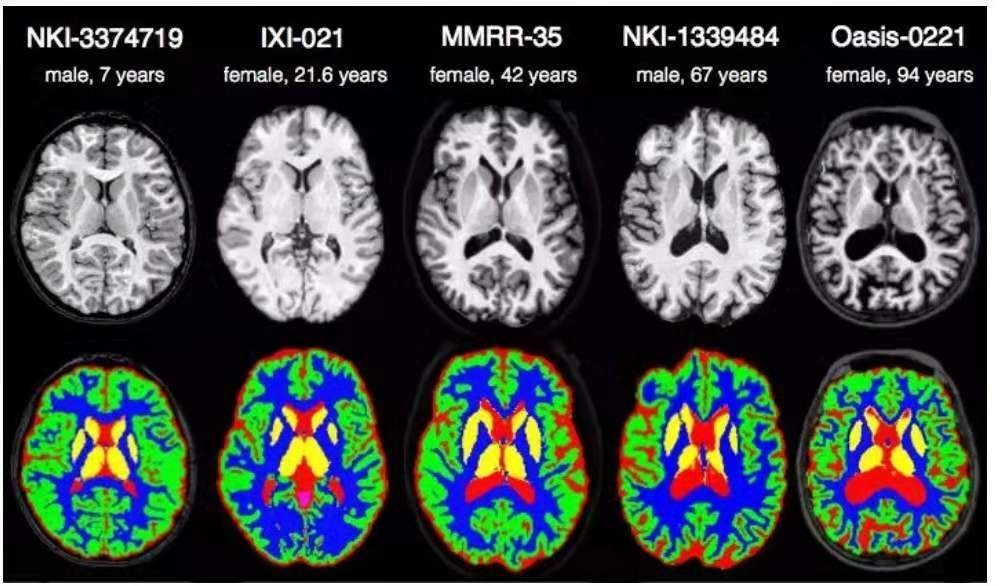

举例而言,在下图中展示了一种肺部CT切片的可视化结果。该图像经过预处理后已被转换为灰度图像状态,并呈现明显的组织与器官界限。而图二则展示了不同个体的脑MRI图像数据,则显示出显著差异性特征。这对脑组织的具体提取工作而言确实存在诸多挑战性问题。

图二 不同个体的脑MRI成像结果